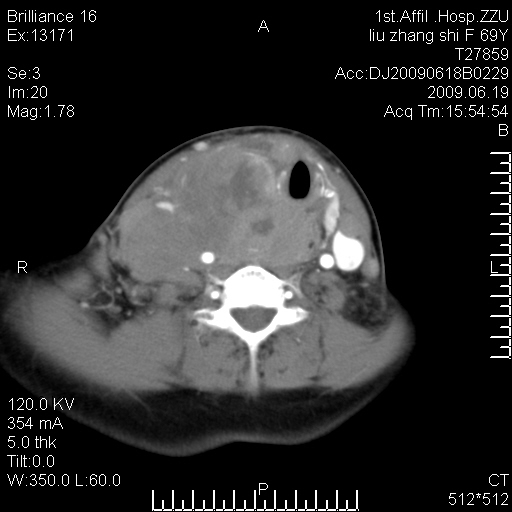

标题: CT26782:女,69岁,颈部占位,3天后公布病理结果。

【病理证实系列】女,69岁,颈部占位,有病理结果,3天后公布。(由于病例时间较久,临床资料不全,请网友见谅)本系列将有几百种常见、少见及罕见病例,均经病理证实。病例资料来自郑州大学第一附属医院。与网友共享,本人有空就发。

甲状腺癌并颈部淋巴结转移。感谢楼主的良苦用心,谢谢。

甲状腺癌并颈部淋巴结转移。

需与鼻咽癌鉴别!

支持甲状腺癌广泛侵及周围结构并颈部淋巴结转移。

鉴别:淋巴瘤、恶性神经源性病变、恶性纤维组织细胞瘤。

病理结果:颈部非霍奇金淋巴瘤。